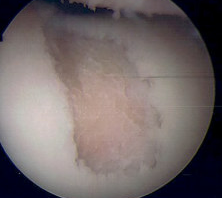

AMIC procedure of a full thickness patella lesion

Operative options for focal chondral defects of the patella

Debridement